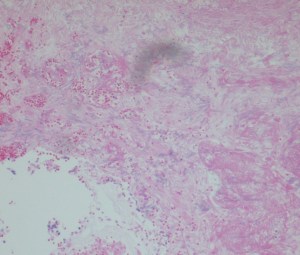

The histology on H&E stain shows areas of necrosis with faint septate hyphae as well as broad, ribbon-like hyphae within the vasculature. The silver stain nicely highlights the broad hyphae which we can identify as a zygomycete. The silver stain also accentuated the massive amounts of thinner hyphae with parallel walls and 45 degree branching which is consistent with aspergillus. This patient was found to have both an aspergillus infection which caused the positive serum antigen test, but then also developed a zygomycete infection which led to his death. We did not identify aspergillus on our fungal culture which may be explained by several possibilities. Our patient had been treated with voriconazole for a potential aspergillus infection which may make it more difficult for the aspergillus to grow on fungal culture. Zygomycetes are rapid growers which could have inhibited the growth of another organism or could have inhibited our ability to identify a second organism growing on the plate.